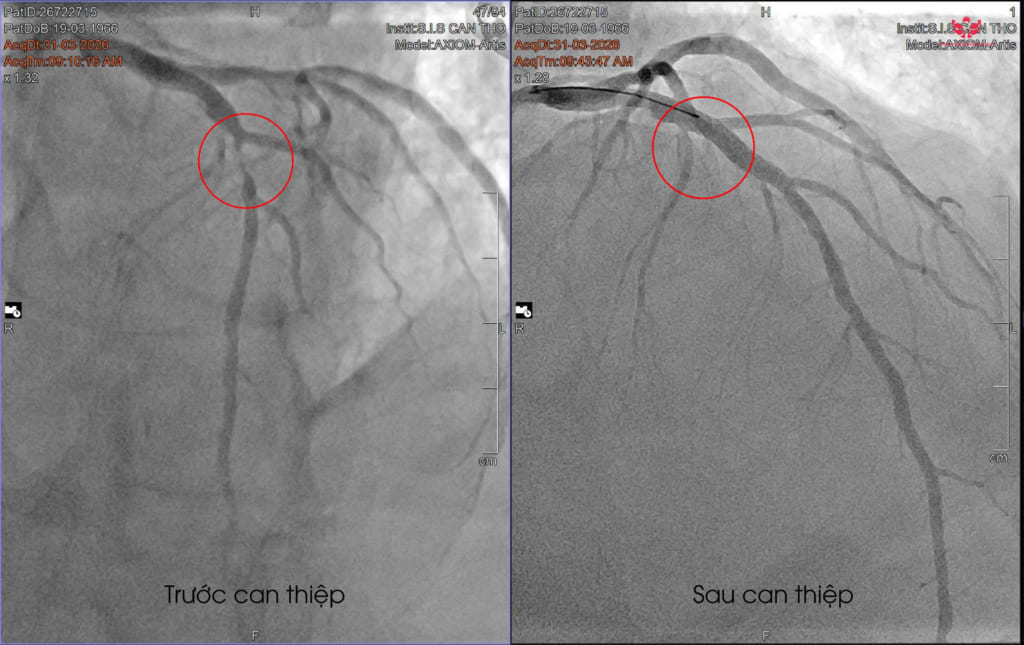

Bệnh nhân nhanh chóng được chỉ định chụp mạch vành bằng DSA. Kết quả khiến ê-kíp bác sĩ không khỏi lo ngại khi ghi nhận động mạch liên thất trước (mạch máu nuôi sống phần lớn cơ tim) bị hẹp nặng, gần như tắc hoàn toàn.

“Đây là động mạch rất quan trọng, chi phối khoảng 50–60% cơ tim. Nếu tắc hoàn toàn, bệnh nhân có thể đột tử bất cứ lúc nào…” BS. Mai Hoàng Dil cho biết.

May mắn, trong trường hợp này, dòng máu vẫn còn lưu thông rất nhỏ, “như sợi chỉ”, giúp bệnh nhân chưa rơi vào biến chứng nguy hiểm như đột tử. Ngay sau đó, bệnh nhân được chỉ định can thiệp đặt stent phủ thuốc, dưới sự hỗ trợ của siêu âm trong lòng mạch IVUS nhằm tối ưu hiệu quả điều trị.